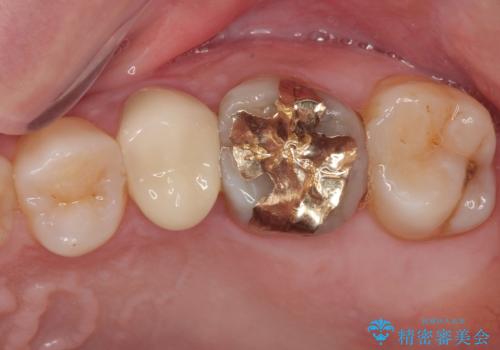

「他の歯も、せっかくなら精度の良いものに替えておきたい」とのご希望があり、

上顎左側第一大臼歯

下顎左側第一大臼歯

に入っていた保険診療の銀歯(メタルインレー)を、精度の良いゴールドインレーへやり替えを行いました。